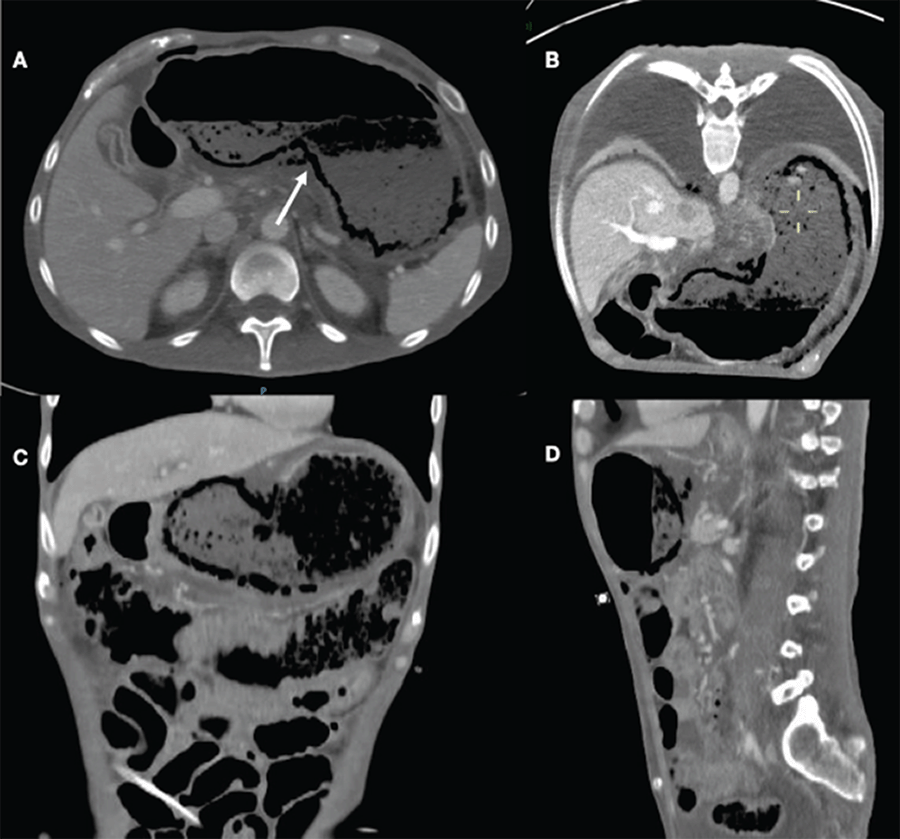

A 42-year-old male with a history of type 2 diabetes mellitus, diabetic neuropathy, diabetic retinopathy, chronic kidney disease on peritoneal dialysis, autonomic neural dysfunction, with a past surgical history of peritoneal dialysis catheter placement; was hospitalized for diagnostic workup of chronic diarrhea. During his hospital stay, he developed acute and severe abdominal pain associated with hemodynamic instability requiring fluid resuscitation and vasoactive drugs. A CT scan showed gastric pneumatosis predominantly in the gastric fundus and lesser curvature, absence of mucosal enhancement, perigastric free air, and no signs of arterial or venous thrombosis (Figure 1). Due to these findings, an exploratory laparotomy was performed in which clear abdominal free fluid was found. Due to necrosis of the gastric fundus and lesser curvature, a total gastrectomy with Roux-en-Y esophagojejunostomy was performed. He was admitted to ICU and, due to favorable evolution, was admitted to the hospital ward to continue his recovery. The pathology report showed acute infectious gastritis with abscess formation, extensive mucosal necrosis, and acute peritonitis (Figure 2). Additionally, gram-positive bacilli were identified, and the peritoneal fluid culture was positive for Lactobacillus fermentans.

Figure 1. Abdominal CT Scan. Published With Permission

Gastric wall thickening associated with gastric pneumatosis and absence of mucosal enhancement predominantly in lesser curvature.